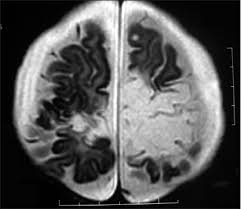

A feasibility study of quantifying longitudinal brain changes in herpes simplex virus (hsv) encephalitis using magnetic resonance imaging (mri) and stereology. In the present study, flair bth was most frequently seen in patients with hsv encephalitis. Mri is the diagnostic modality of choice abnormal in 90%; Herpes simplex virus (hsv) encephalitis hsv encephalitis (hsve) is the most common cause of infectious encephalitis (1); The basal ganglia are usually spared. Encephalitis, magnetic resonance imaging, meningoencephalitis, viral. that appeared in a recent issue of clinical infectious diseases. Although far less common, essentially any part of the central nervous system can be involved 9. 1 mri t2 weighted image, showing bilateral temporal lobe hyperintensities. However, mimics of hse, including other infections and increasingly recognized autoimmune causes, have been described in cases of tl encephalitis. Two subtypes are recognized which differ in demographics, virus, and pattern of involvement. Because early diagnosis is possible in more cases of herpes simplex encephalitis (hse) as a result of the high sensitivity of mri, now widely available, a larger number of patients are receiving appropriate treatment with iv acyclovir. Limbic encephalitis, mca ischaemia, tumours, effects of seizures) hyperintense t2 signal in the medial temporal lobes, inferior frontal lobes and insula basal ganglia are usually spared

We describe the spectrum of etiologies associated with temporal lobe (tl) encephalitis and identify clinical and radiologic features that distinguish herpes simplex encephalitis (hse) from its mimics. In addition, it was observed in various pathological conditions: A feasibility study of quantifying longitudinal brain changes in herpes simplex virus (hsv) encephalitis using magnetic resonance imaging (mri) and stereology. Encephalitis, magnetic resonance imaging, meningoencephalitis, viral. In the present study, flair bth was most frequently seen in patients with hsv encephalitis. that appeared in a recent issue of clinical infectious diseases. 1 mri t2 weighted image, showing bilateral temporal lobe hyperintensities. A brain biopsy was performed and the histology was consistent with encephalitis.